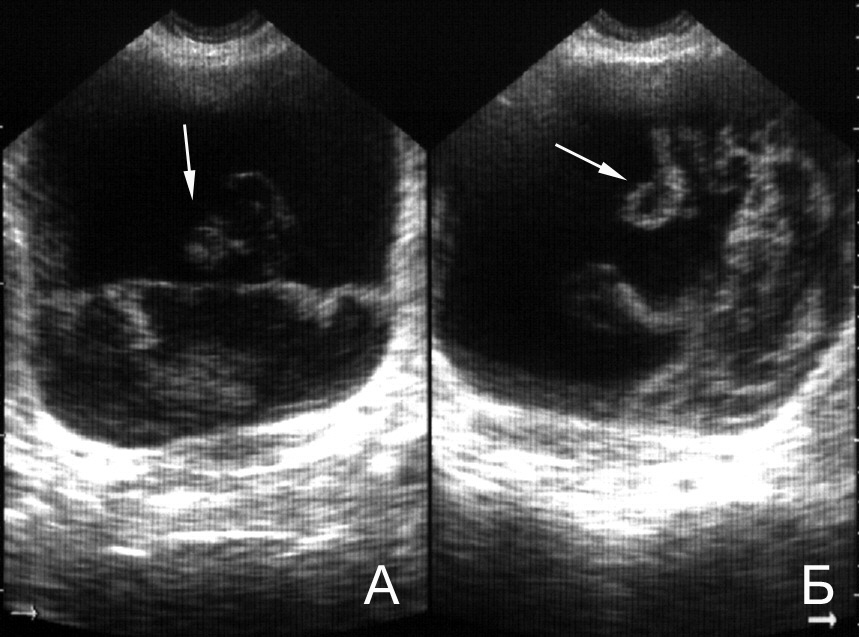

Рис. 16. Мочевой пузырь при цистите, лейкоцитурии. Определяется горизонтальный уровень нежной эхоструктуры (обозначен стрелкой), изменяющий свою форму и локализацию при перемене положения тела. (Поперечное сканирование, А − в положении пациента на спине, Б − на левом боку. Конвексный датчик 5 МГц, “Logiq-500”).